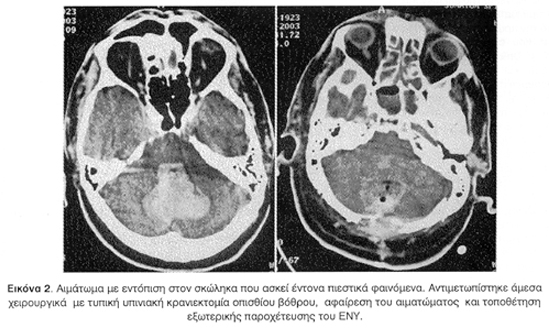

Εννιά (9) περιστατικά αντιμετωπίστηκαν χειρουργικά (6 άμεσα, 3 όψιμα), ενώ τα υπόλοιπα έντεκα ακολούθησαν συντηρητική αγωγή. Οι κυριότεροι παράγοντες που λήφθηκαν υπόψη για την επιλογή του τρόπου θεραπείας ήταν η ηλικία των ασθενών, η αρχική κλίμακα Γλασκώβης (GCS), η ανάπτυξη ή όχι αποφρακτικού υδροκεφάλου και το μέγεθος του αιματώματος. Χειρουργικά αντιμετωπίστηκαν ασθενείς με GCS <13, ημισφαιρικά παρεγκεφαλιδικά αιματώματα με διάμετρο >30x40 χιλ., αιματώματα στο σκώληκα >25x35 χιλ, και αιμορραγίες που προκαλούσαν αποφρακτικό υδροκέφαλο.

Όπως φαίνεται και στο σχετικό πίνακα η πλειονότητα των περιπτώσεων ήταν αιμορραγίες που αφορούσαν στα παρεγκεφαλιδικά ημισφαίρια (14, 70%). Αρχική αποκλειστική εντόπιση στο σκώληκα απαντήθηκε σε τέσσερα (4) περιστατικά (20%), ενώ μικτή εντόπιση δηλαδή και στα ημισφαίρια και στο σκώληκα της παρεγκεφαλίδας παρατηρήθηκε μόνο σε δύο (2) ασθενείς (10%) (Πίνακας 1).

Χειρουργικά αντιμετωπίστηκαν εννιά (9) ασθενείς (45%). Η χειρουργική επέμβαση σε έξι (6) περιπτώσεις (30%) πραγματοποιήθηκε μέσα σε δώδεκα (12) ώρες από την κλινική εκδήλωση του συμβάντος και σε τρεις (3) όψιμα (15%), λόγω επιδείνωσης της κλινικής εικόνας ή λόγω διαταραχών πηκτικότητας (3η-6η ημέρα). Σε όλους τους ασθενείς τοποθετήθηκε παροχετευτικό σύστημα του εγκεφαλονωτιαίου υγρού (ΕΝΥ) το οποίο σε έξι (6) περιπτώσεις (30%) συνδυάστηκε και με αφαίρεση του αιματώματος.

Οι έξι (6) ασθενείς που υποβλήθηκαν σε χειρουργική επέμβαση αφαίρεσης του αιματώματος τοποθετήθηκαν σε πρηνή θέση. Μετά από μέση τομή που εκτεινόταν από την έξω ινιακή ακρολοφία έως την ακανθώδη απόφυση του δεύτερου αυχενικού σπονδύλου διενεργήθηκε υπινιακή κρανιεκτομία. Ακολούθησε η διάνοιξη της σκληράς μήνιγγας και τομή στο φλοιό της παρεγκεφαλίδας. Κατόπιν έγινε προσπάθεια κένωσης του αιματώματος με καταιονισμό ύδατος, χρήση αναρρόφησης και με λαβίδα βιοψίας όγκου. Στην περιοχή επιτεύχθηκε επιμελής αιμόσταση. Δόθηκε μεγάλη σημασία στη στεγανή σύγκλειση της σκληράς μήνιγγας και στη λεπτομερή συρραφή των μυϊκών στιβάδων σε τρία στρώματα.

Η εντόπιση της αιμορραγίας περιφερικά στα ημισφαίρια ή κεντρικά στο σκώληκα επηρεάζει σε σημαντικό βαθμό την επιλογή για θεραπευτική αντιμετώπιση και την πρόγνωση. Η περιοχή της αιμορραγίας είναι συνήθως κοντά στον οδοντωτό πυρήνα στο έδαφος της άνω παρεγκεφαλιδικής αρτηρίας και όχι στη μέση γραμμή. Αιματώματα με κεντρική εντόπιση έχουν συνήθως πιο βαριά πρόγνωση δεδομένου ότι ασκούν πιο εύκολα και πιο έντονα πιεστικά φαινόμενα στο στέλεχος και στην 4η κοιλία7,9,13,15,18,21.